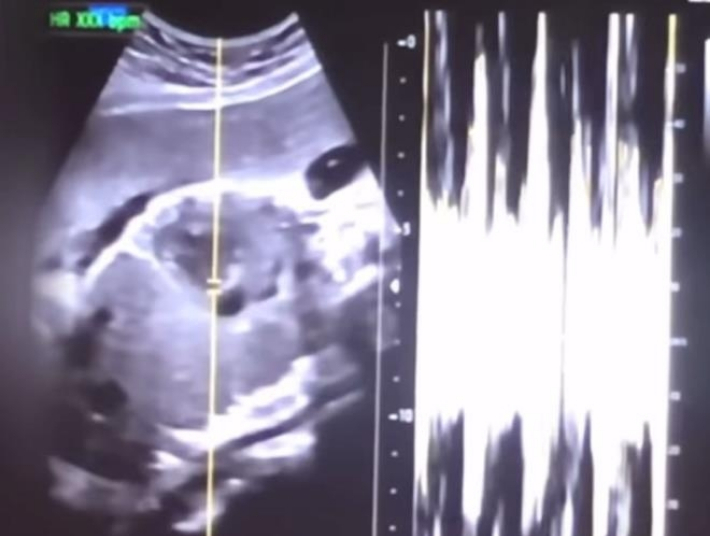

낙태한 산모의 유튜브 동영상에서 캡쳐한 초음파 사진과 심박 그래프. 연합뉴스낙태한 산모의 유튜브 동영상에서 캡쳐한 초음파 사진과 심박 그래프. 연합뉴스